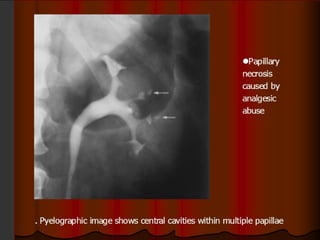

GU Tb-IVU

The most common findings being

hydrocalycosis,hydronephrosis, or hydroureter due to

stricture formation .

 Early signs include the moth-eaten appearance of

calyceal erosion and papillary irregularity- signs are

best seen on early excretory films.

Cavitary lesions communicating with the collecting

system are characteristic of TB.

 These lesions eventually enlarge as parenchymal

destruction ensues.